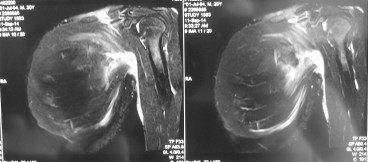

An MRI scan of his left pectoralis major muscle was performed. It confirmed a tear of the left pectoralis major muscle. The muscle and tendon usually rips off the insertion into the humerus bone. In his case, the tendon was still attached to the humerus bone but the muscle was torn in the junction between muscle and tendon (musculotendinous junction).